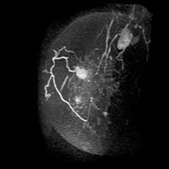

画像中间浅淡白色部分为癌 (治疗前)

治疗6个月后,白色部分变小

治疗一年后白色部分有明显缩小的变化